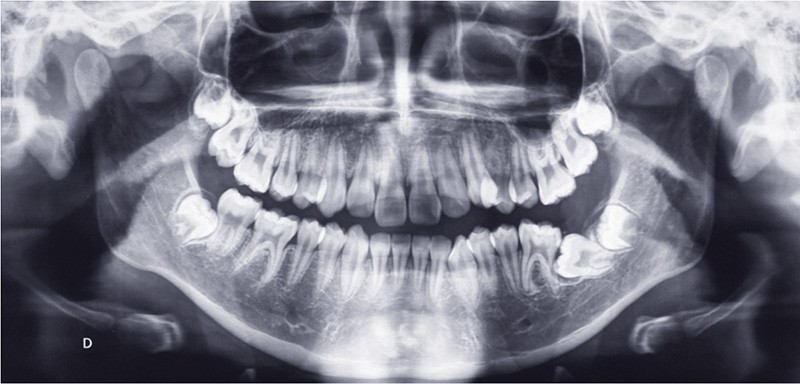

Sur le plan dentaire, au maxillaire, le patient présente une arcade en lyre avec de nombreuses malpositions (fig. 4). À la mandibule, la 37 est absente de l’arcade (fig. 5). Le patient présente une classe I d’Angle droite et gauche (fig. 6 et 7). Le surplomb et le recouvrement sont satisfaisants, les milieux sont alignés, et il existe une occlusion inversée 22/33 (fig. 8).

Le patient présente une DDM par encombrement antérieur et postérieur, des incisives mandibulaires vestibulo-versées et une 37 incluse en position horizontale (fig. 9).